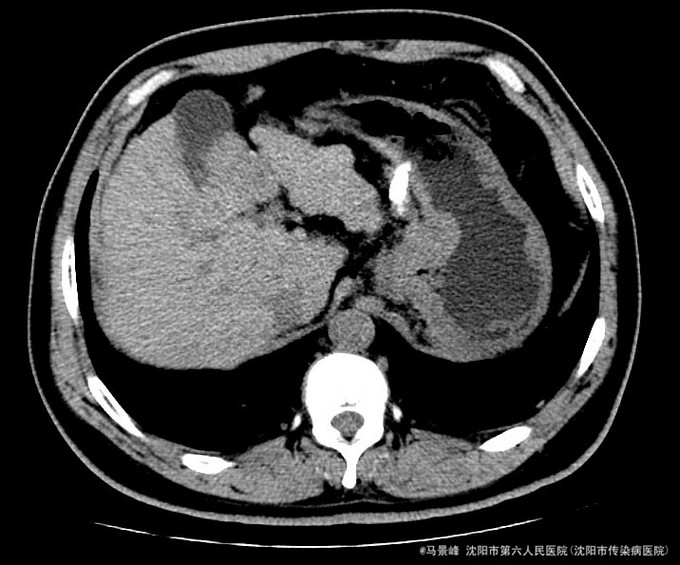

查体:巩膜无黄染,心肺听诊无异常,腹软,无压痛,肝脾肋下未触及,移动性浊音阴性,双下肢无浮肿。 入院后化验结果:丙氨酸氨基转移酶 24 U/L、天门冬氨酸氨基转移酶 36 U/L、碱性磷酸酶 101 U/L、γ-谷氨酰转肽酶 96 U/L、胆碱酯酶 6127 U/L、总蛋白 80.8 g/L、白蛋白 41.4 g/L、总胆红素 30.0 umol/L、结合胆红素 0.0 umol/L、非结合胆红素 16.5 umol/L、δ胆红素 13.5 umol/L。葡萄糖 7.77 mmol/L。乙型肝炎病毒表面抗原 阳性(+) 、乙型肝炎病毒核心抗体 阳性(+) 。甲胎蛋白 3.49 ng/mL。 CT检查示:肝脏形态不规整,肝裂增宽,肝尾叶体积相对增大,各叶大小比例失调,肝实质密度不均,肝内可见多个大小不等结节影,较大者位于肝Ⅳ段胆囊旁,其边缘可见条状碘油沉积,大小约3.3x3.05cm,增强扫描动脉期其边缘轻度强化,门脉期及延迟期扫描呈稍低密度,病灶内坏死区未见强化,其余结节无明显强化,较大者位于Ⅷ段,约1.2cm大小,延迟期呈稍低密度,门脉主干及左右支纤细,左支充盈欠佳,脾脏缺如,胆囊不大,壁增厚,其内密度均匀,胰头区可见一囊性密度影,大小约2.11cm,增强扫描无强化。肝内外胆管未见明显扩张,食管下段胃底贲门区见扩张扭曲的血管影,腹膜后未见明显肿大淋巴结。 患者CT所见胆囊旁病灶碘油流失,且动脉期仍有强化,提示肿瘤仍有血供。

诊断:1、乙肝肝硬化 失代偿期;2、原发性肝癌TACE术后 治疗:入院后除加强休息、抗病毒治疗外,行增强CT检查,发现肝癌TACE治疗后胆囊旁病灶碘油流失,且动脉期仍有强化,提示肿瘤仍有血供。遂于局麻下再次行TACE治疗。